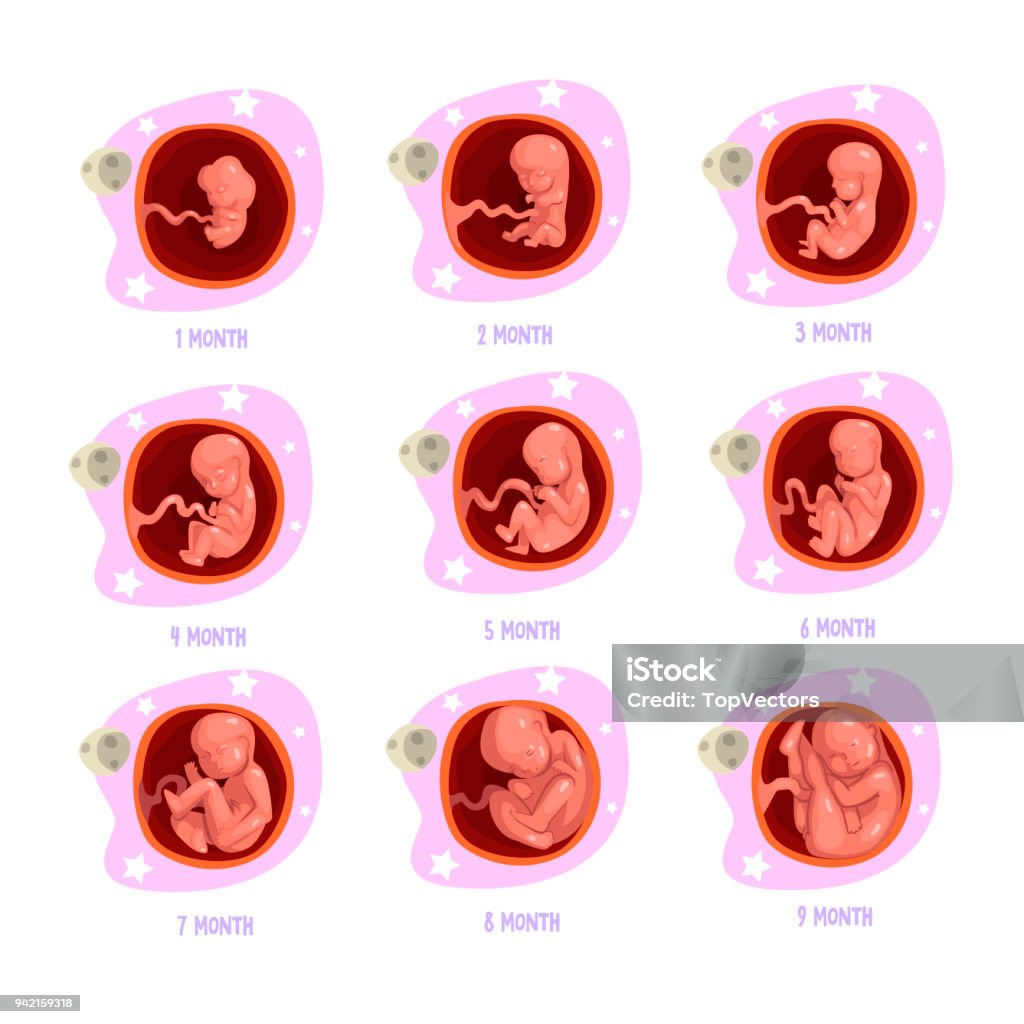

月成長過程で胚を胎児。人間の妊娠胎児または子の胎児妊娠の出生前のプロセス。ベクトル フラット インフォグラフィックのアイコンを設定のイラスト素材・ベクター Image 86554938。

子宮内の胚、セット。妊娠のさまざまな段階における胎児の発育と成長Premiumベクトル素材。

9 月 1 日から妊娠のプロセス胎児の発育子宮の中の赤ちゃんの成長ベクター インフォ グラフィック ポスターやパンフレットのデザイン -イラストレーションのベクターアート素材や画像を多数ご用意 - iStock。